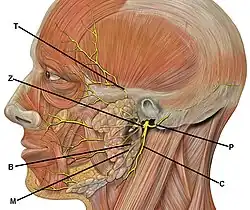

The facial nerve and parotid duct should be examined for any potential damage when the buccal mucosa is involved.